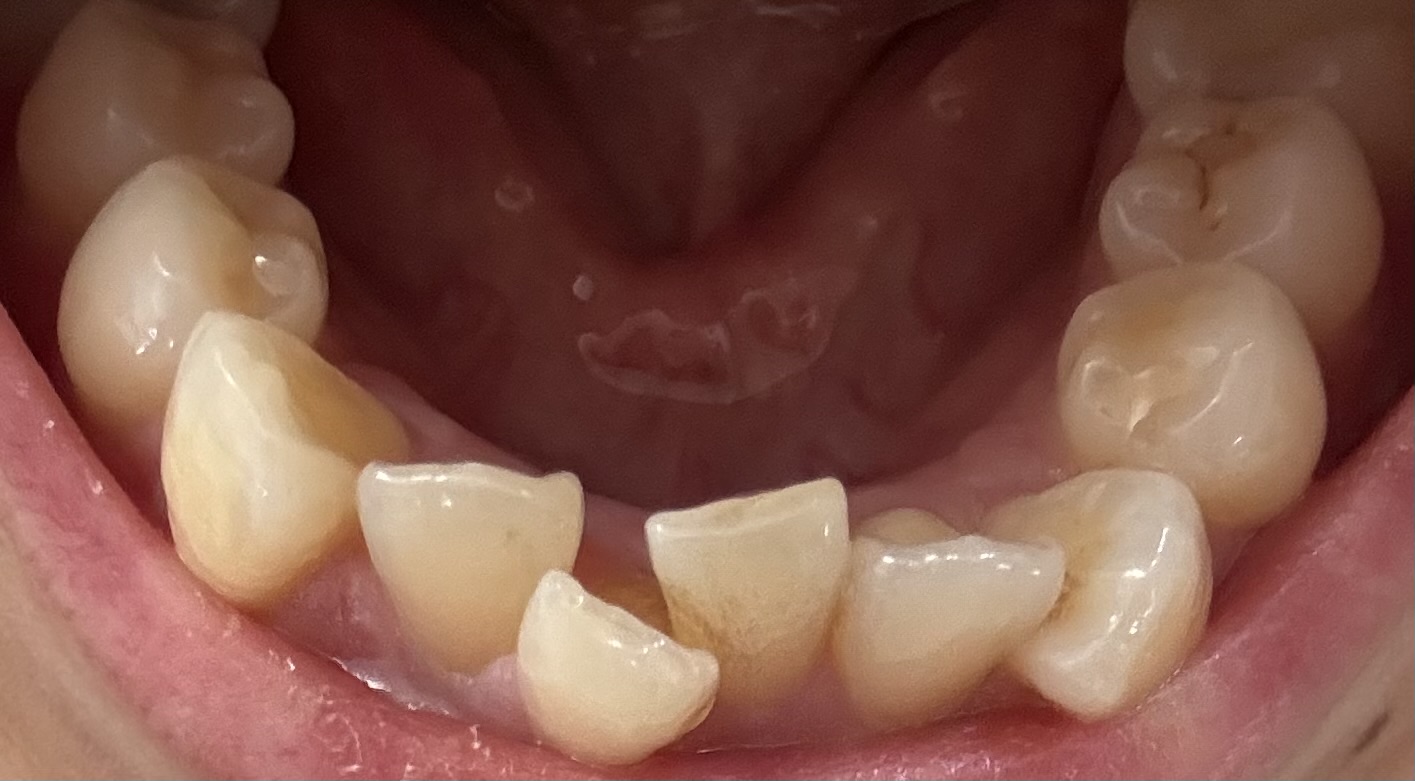

右上は2番を抜歯、左上は4番を抜歯、下に関しては上の様子を見てそのうち片側の4番か前に出ている1番どちらか1本の抜歯になると言われました。

奥歯の噛み合わせを考えて3本抜歯になりそうとは他の医院でも言われた事があったので納得したのですが、前後に重なっているとは言え2番の抜歯は予想外だったので先生に理由を聞くと、

写真拝見しました、写真から伺えることは右上2番の抜歯は避けられないように思います、右下1番も抜歯になる可能性は高いように思います。

一般的な叢生と全く違うので定型的な4番抜歯にはなりそうには思えません。

特異的な抜歯ですが歯並びがそもそも特異的ですから2番抜歯で3前歯で仕上げることになります。

上顎側切歯が口蓋側に転移しており、犬歯と中切歯との間にスペースないという症例は時々拝見することがあります。

その際、小臼歯を抜歯するのか、側切歯を抜歯するのかと考えることはあります。

ただ、側切歯を抜歯した場合、前歯部の配列状態が、通常とはかなり異なる形になり、それは犬歯の尖頭を落としてもやはり違和感がぬぐえない歯並びになります。

ということからすれば、側切歯に特段の問題がないのであれば、通常の小臼歯抜歯を極力選びたいところです。